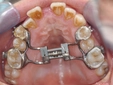

Dogo Çenesinin Gücü Ne Kadar Ton Basabiliyor?Dogo Argentino, güçlü yapısıyla dikkat çeken bir köpek ırkıdır. Bu ırk, av köpeği olarak yetiştirilmiş olup, kaslı yapısı ve güçlü çenesi ile bilinir. Dogo Argentino'nun çene gücü, hem avcılık yetenekleri hem de koruma işlevleri açısından oldukça önemlidir. Bu makalede, Dogo'nun çene gücünü detaylı bir şekilde inceleyeceğiz. Dogo Argentino'nun Çene AnatomisiDogo Argentino, güçlü bir çene yapısına sahip olmasıyla birlikte, bu güçlü yapı birkaç anatomik özellikten kaynaklanmaktadır:

Çene Gücü ve Basınç ÖlçümüBir köpeğin çene gücünü ölçmek için genellikle "bite force" (ısırma gücü) terimi kullanılır. Dogo Argentino'nun çene gücü, 450 psi (pound per square inch) civarında ölçülmüştür. Bu, Dogo'nun çenesinin yaklaşık 20-30 ton basma kapasitesine sahip olduğu anlamına gelir. Bu güç, Dogo'nun avını yakalama ve tutma yeteneğini büyük ölçüde artırır. Çene Gücünün ÖnemiDogo Argentino'nun çene gücü, birkaç açıdan önem taşımaktadır: